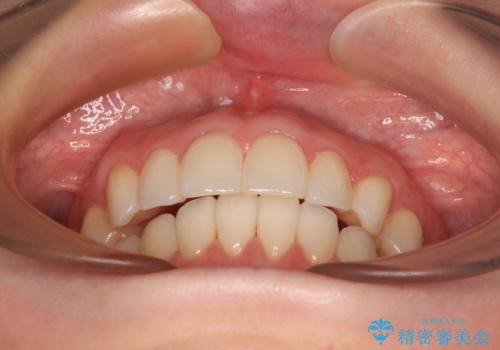

前歯のデコボコをインビザラインで改善

- 前歯のデコボコや八重歯の様になっていることを気にして来院された患者様です。

犬歯捻れて前方に飛び出しており、下顎前歯もそれに沿うようにデコボコとなっていました。

IPR(歯と歯の間を削る処置)によりスペースを獲得して上下顎前歯のデコボコを改善し、前歯が前方に突出しないように設定した上で、インビザラインにて矯正治療を行うこととしました。